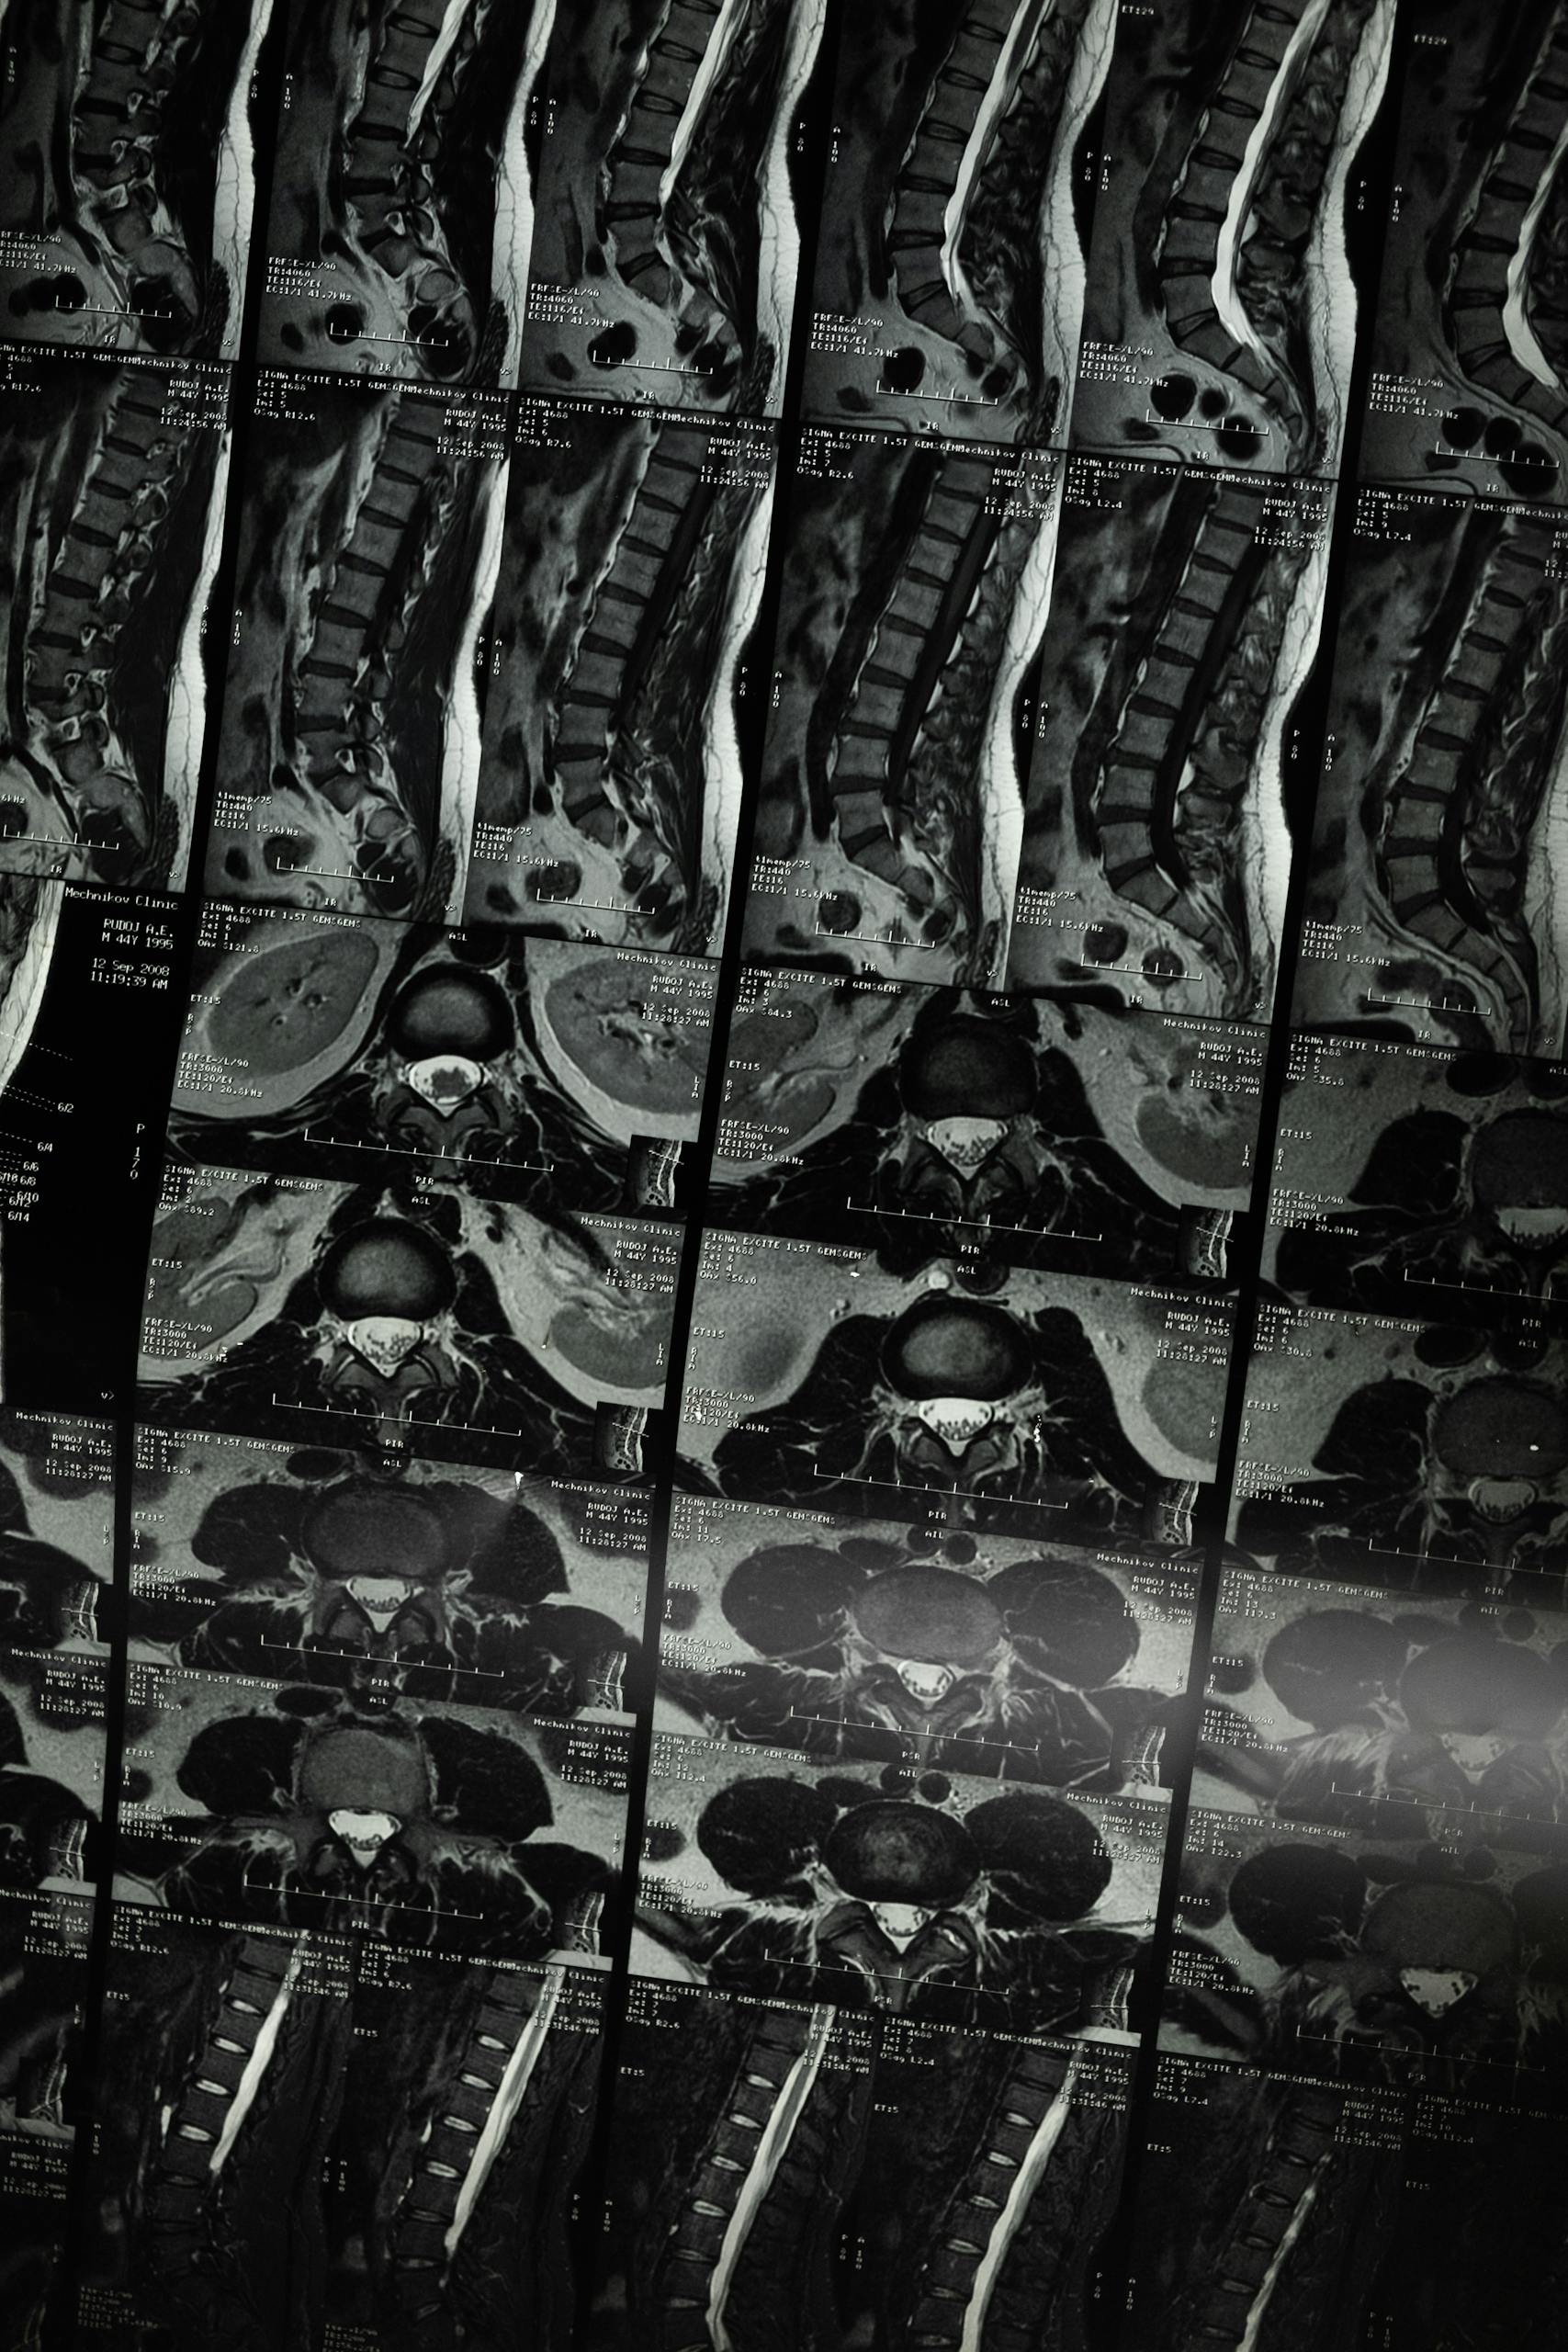

Magnetic Resonance Imaging (MRI)

An MRI (Magnetic Resonance Imaging) is a medical scan that uses strong magnets and radio waves (not X-rays) to create detailed pictures of your body’s internal structures, especially soft tissues like the brain, spinal cord, muscles, and spinal discs, by detecting signals from water molecules in your body. It’s a safe, non-invasive way for doctors to diagnose conditions, view anatomy, and monitor treatments, producing cross-sectional “slices” of the body.

While we don’t have in-house MRI capabilities, we will assist with getting your MRI scheduled, expedited and authorized if required.